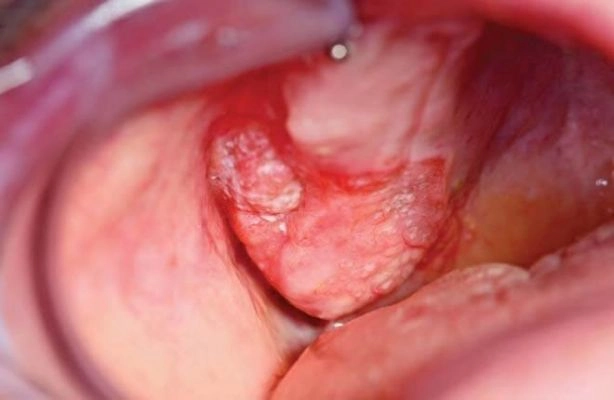

Bạn sẽ sốc khi nhìn thấy hình ảnh bệnh sùi mào gà thực tế: những mảng u nhú xù xì, mọc chồng chất như mào gà, tập trung ở bộ phận sinh dục, hậu môn hoặc miệng. Đây không còn là lý thuyết, mà là minh chứng rõ ràng cho sự nguy hiểm của căn bệnh xã hội này. Đừng nhắm mắt làm ngơ – hình ảnh chân thực sẽ giúp bạn nhận biết sớm và tránh biến chứng kinh hoàng.

Nếu bạn chưa từng thấy tổng hợp ảnh bệnh sùi mào gà, thì đây là lúc đối diện với sự thật: loạt hình ảnh được chụp từ thực tế phòng khám, phản ánh mức độ lan rộng và tàn phá của virus HPV lên cơ thể con người. Không chỉ đơn thuần là mẩn đỏ hay ngứa ngáy – đây là ác mộng về sức khoẻ sinh sản nếu không điều trị kịp thời.

Hình ảnh bệnh sùi mào gà ở miệng có thật

Hình ảnh bệnh sùi mào gà ở miệng dễ bị nhầm với nhiệt miệng